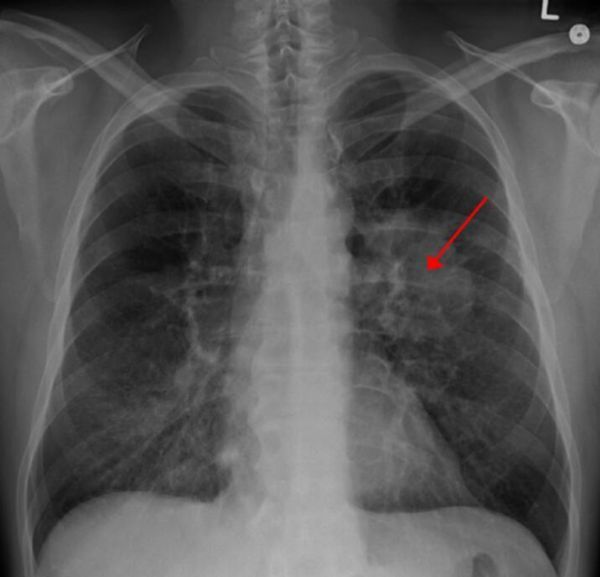

【3】Nat Commun:一种诊断且治疗肺癌的新方法

doi:10.1038/ncomms11702

近日,一项刊登于国际杂志Nature Communications上的研究报告中,来自新加坡的研究人员通过研究发现了一类名为oncomiRs的小RNA分子,其是引发肺癌发生的主要原因,相关研究或为理解肺癌对疗法产生耐药性的机制,以及有效监测并且开发治疗肺癌的新型疗法提供思路。

文章中,研究者揭示了,肿瘤内罕见的癌症干细胞对常规疗法会产生耐受性,这就常常会引发肺癌患者疾病复发,由于oncomiRs分子是癌症干细胞的主要驱动子,因此剔除oncomiRs分子的新型疗法或许可以帮助我们杀灭癌症干细胞,为此研究人员利用了一系列名为锁核酸(locked nucleic acid,LNA)的治疗方法,该方法可以抵御癌症干细胞中的oncomiRs分子,研究者表示,这种方法可以成功阻断小鼠模型中人类肺部肿瘤的生长,如今研究者们正在同制药公司联合开发一种可以直接用于人类机体的新型药物。